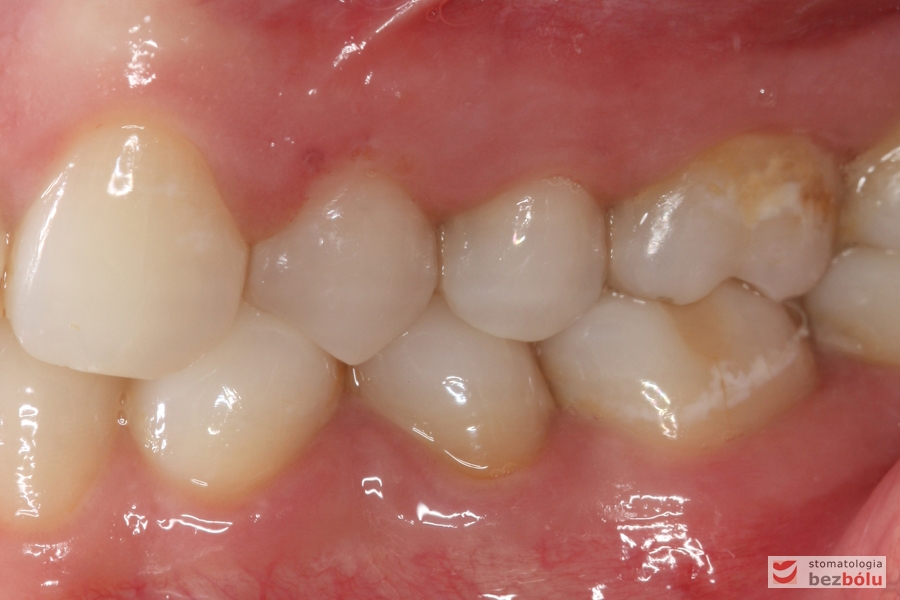

Nadmiar miejsca po brakującej "piątce" po stronie prawej wykorzystany do rekonstrukcji "szóstki", utrzymana mezjorotacja "siódemki" zamykającej luki

Nadmiar miejsca po brakującej „piątce” po stronie prawej wykorzystany do rekonstrukcji „szóstki”, utrzymana mezjorotacja „siódemki” zamykającej luki